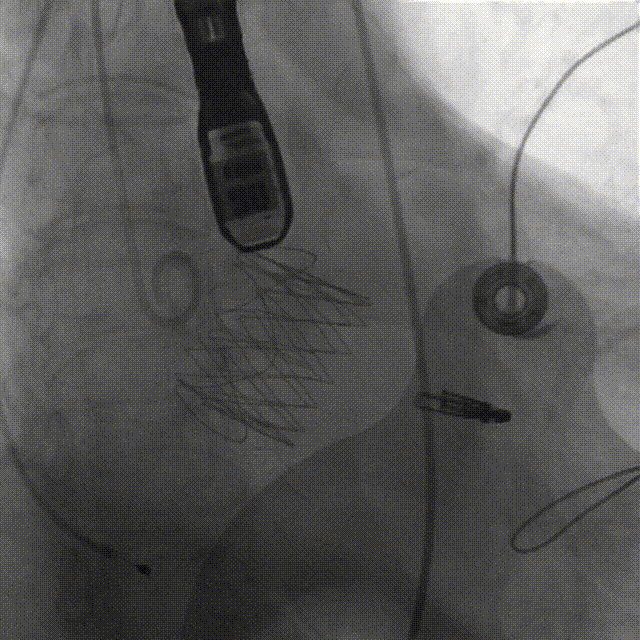

经心尖TAVR

主动脉根部造影后,介入器跨瓣:

定位件进入窦部:

将瓣膜件降至合适水平面:

释放瓣膜后,复查根部造影,未见明显反流,瓣膜形态和位置满意,双侧冠脉显影良好:

复查超声显示主动脉瓣架深度合适、位置稳定,瓣叶启闭正常,未见明显瓣周反流: